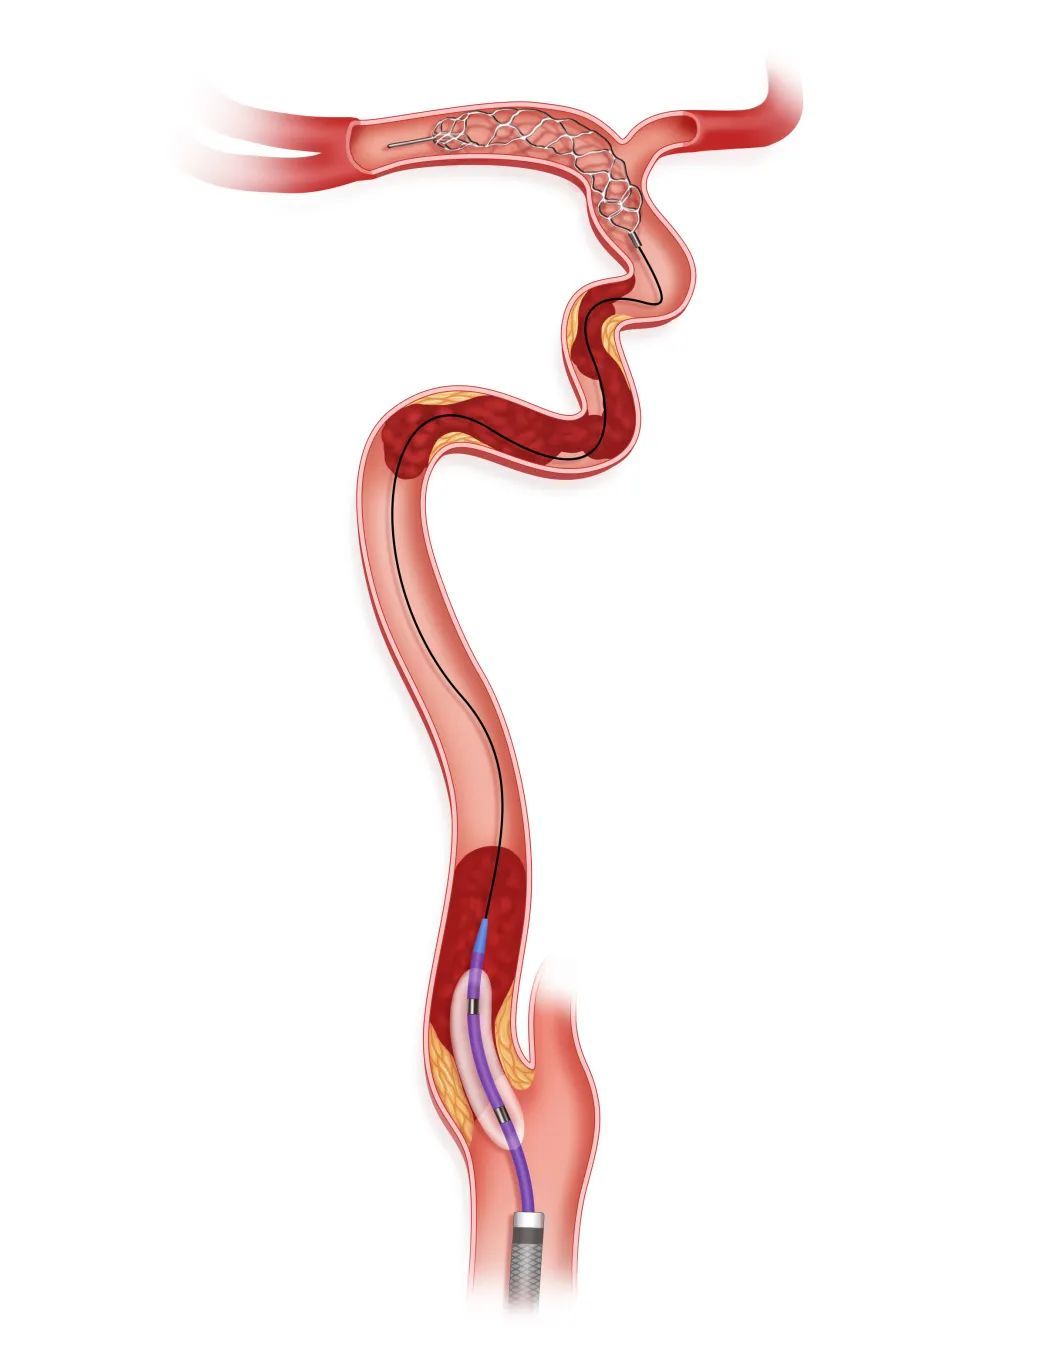

步骤一

释放Syphonet®取栓支架远端保护

微导丝微导管突破闭塞段后,将Syphonet®取栓支架跨越M1段与颈内动脉末端释放,起到颅内远端血管的保护作用。